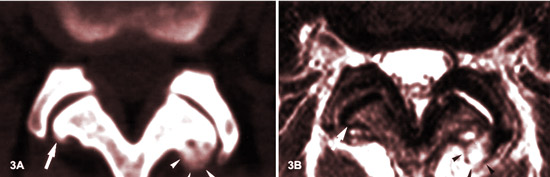

ARTHROSE FACETTAIRE (spondylarthrose) ET SON APPARENCE IRM :

LES STADES

Source: MR imaging and CT in osteoarthritis of the lumbar facet joints.